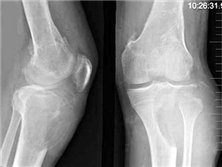

骨纖維結(jié)構(gòu)不良是一種以纖維、骨組織類腫瘤樣增生為特點(diǎn)的非遺傳性疾患,又稱為骨纖維異樣增殖癥??杀憩F(xiàn)為單個(gè)骨組織或多骨病損,以畸形、疼痛和病理骨折為特點(diǎn)。約3%的多骨病損患者伴有內(nèi)分泌紊亂,常見為性早熟和皮膚“牛奶咖啡斑”樣病損(McCune-Albright綜合征),極少數(shù)可出現(xiàn)肉瘤變。

Q: 骨纖維結(jié)構(gòu)不良影像學(xué)表現(xiàn)

A: 骨纖維結(jié)構(gòu)不良的影像學(xué)表現(xiàn)主要有骨質(zhì)膨脹變形、磨玻璃樣改變、囊狀透亮區(qū)、骨皮質(zhì)...